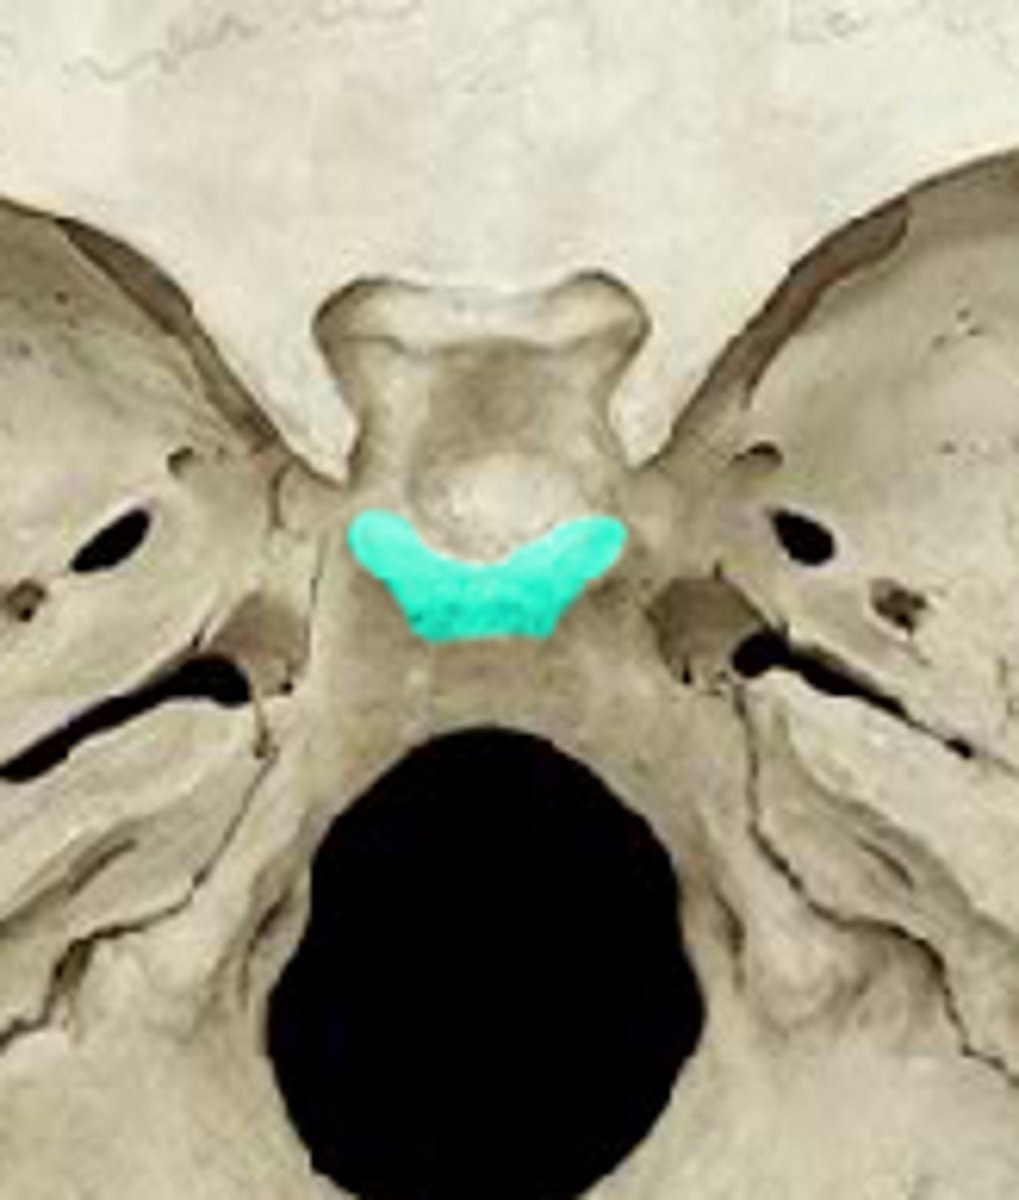

sella turcica

tuberculum sellae

dorsum sellae

posterior clinoid processes

clivus